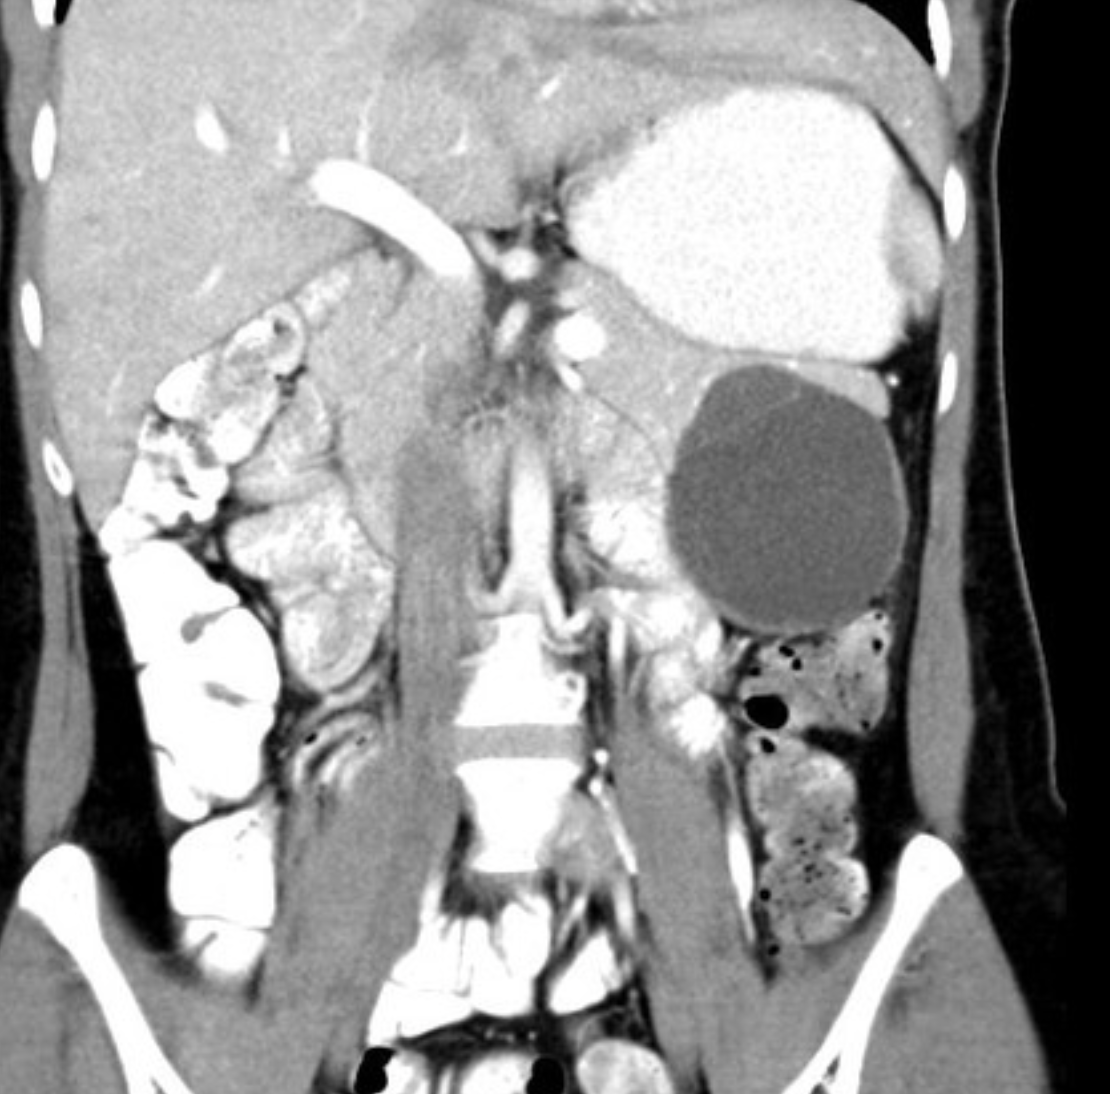

Findings: A well-defined rounded exophytic cystic lesion measuring 6.3 x 7 x 7 cm is seen originating from the tail of the pancreas. It has an average density of 8 HU and shows mild peripheral enhancement on post contrast study. A few thin septations and a tiny mural calcification are seen in it. No solid component is seen in it. Morphology of the remaining pancreas is unremarkable.

Impression: Well-defined rounded exophytic cystic lesion originating from the tail of the pancreas, which is likely, a mucinous cystadenoma of the pancreas (mucinous cystic neoplasm of the pancreas) with possible differential diagnosis of pancreatic pseudocyst (if there is a past history of pancreatitis). Another possible differential can be a hydatid cyst which is however, very unlikely.